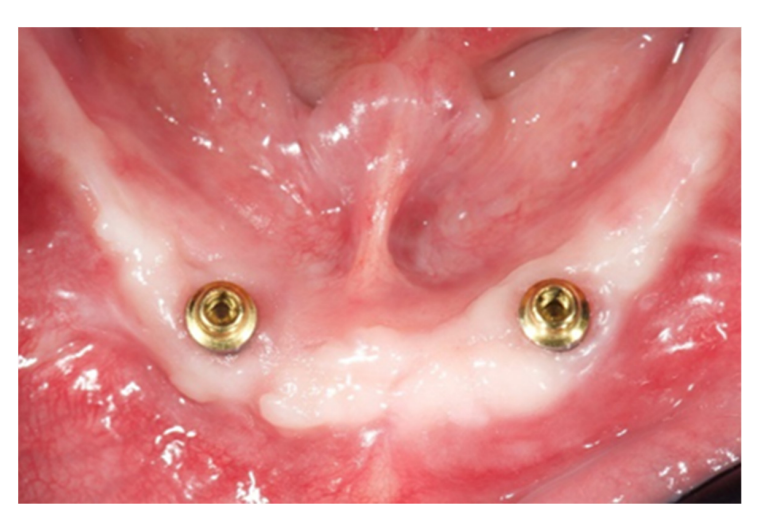

На этом этапе все последующие шаги, от планирования имплантации до доставки окончательных реставраций, были выполнены полностью в цифровом формате. После изготовления новых протезов пациенту был выполнен КТ-сканирование верхней и нижней челюстей по модифицированной технике двойного сканирования. Для последнего на нижнем протезе были применены трехмерные композитные маркеры, а для разделения зубных дуг использован восковый прикус. После этого было выполнено второе сканирование только нижнего протеза с использованием интраорального сканера (Medit i500). В нижней челюсти были запланированы два прямых импланта (Рисунок 4) и установлены (Рисунки 5 и 6) для удержания классического надпротеза.

Имплантаты нижней челюсти были запланированы и установлены параллельно, и на имплантаты сразу же были прикручены соединения OT Equator (Rhein’83, Болонья, Италия). Лоскут был зашит, и окончательная надстройка была подключена к системам крепления на кресле. Через неделю, при удалении швов, имплантаты были нагружены. В верхней челюсти была изготовлена временная реставрация с металлическим усилением, основанная на протезном наборе, до операции (Рисунок 9).